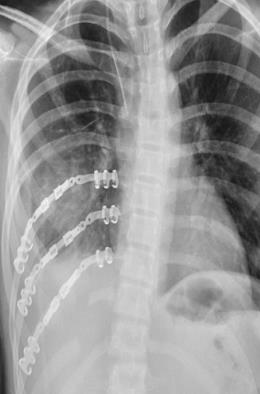

STRACOS™ Strasbourg Costale Osteosynthese System

• The STRACOS (Strasbourg Costale Osteosynthese) System is a titanium chest wall fixation platform that uses malleable rib and sternal clips, rather than plates and screws, to stabilize rib fractures, flail segments, and sternal injuries.

• According to manufacturer information, the 3D rib clips and sternal clips are preassembled and can be bent and twisted in three dimensions to conform to individual rib and sternal anatomy, providing functionally stable but non-rigid osteosynthesis.

• The screwless construct is intended to preserve physiologic chest wall motion while minimizing damage to the intercostal neurovascular bundle.

• Titanium 3D rib clips with 6, 9, or 13 segments in standard and XL widths for transverse, oblique, and comminuted rib fractures, plus straight rib clips and serrated connecting bars for bridging segmental defects.

• Titanium sternal double- and triple-clips in multiple size combinations for Angle of Louis fractures and multi-fragment sternal body fractures.

• Screwless fixation with three-dimensionally formable clips designed to provide functionally stable, flexible osteosynthesis rather than rigid plating; only one universal rib fixation plier is needed for all rib clips.

• Sternal fixation with double and triple clips

• Implant selection:

• Triple sternal clips in small, medium, large, and mixed combinations such as small and small and medium or medium and medium and large are recommended for transverse, oblique, and multi-fragment fractures of the sternal body requiring three clip segments for secure stabilization.

• Double sternal clips in small, medium, large, and mixed combinations are recommended solely for Angle of Louis fractures.

• Sternal width is measured with a dedicated implant sizer inserted into the intercostal spaces, and clip size is selected based on a small, medium, large, or extra-large scale with nominal widths around 29, 36, and 43 millimeters.